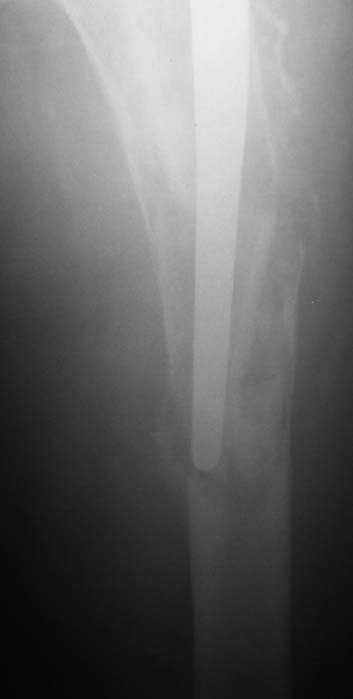

С 2001 г отмечает нарастающие боли в левом бедре. Предполагается удаление протеза, удаление цемена из канала бедра, пластика дефекта бедренной кости.

Нет никакого смысла делать операцию в два этапа. С чашкой все понятно - стандартный подход с установкой пресс-фит компонента. На бедре имеет

место перипротезный перелом В3 типа - т.е. перелом вокруг ножки с ее нестабильностью на фоне выраженного остеолиза. Решение - доступ к каналу

через перелом с удалением самой ножки, костного цемента и рубцовых тканей. Установка ножки дистальной фиксации (типа Solution), длину ножки

надо определить по шаблону. Минимальный контакт ножки с интактной костью - 6-8 см. Фрагменты проксмального отдела собираются на ножке

эндопротеза, дефекты костной ткани заполняются чипсами (аллографт) и фиксируются кортикальными аллографтами, уложенными дополнительно по типу

"вязанки хвороста" серкляжом. Мы имеем 8 или 10 подобных наблюдений и результатами довольны.